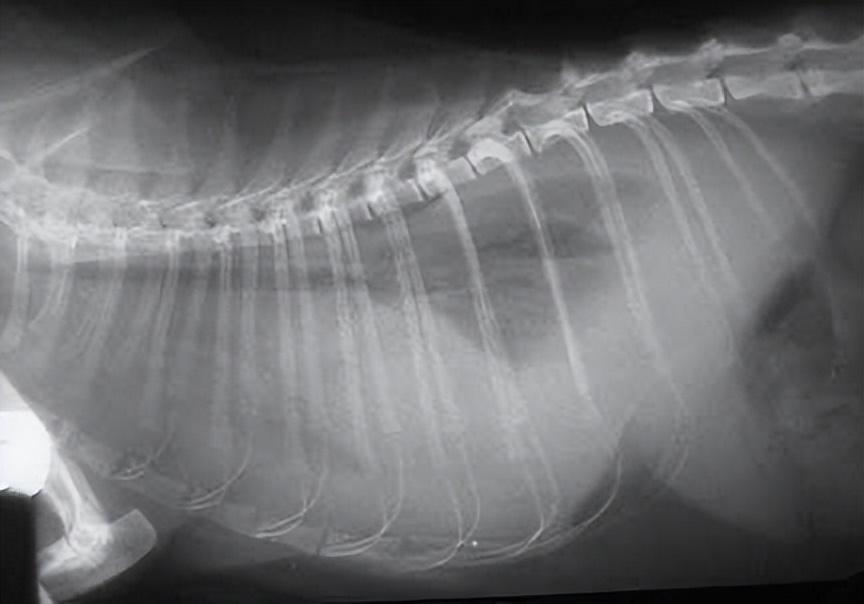

- 胸部 X 光片可能会显示肺部的斑片状密度

这只猫的胸部有大量液体,因此很难识别正常器官。肺部无法完全扩张,导致呼吸困难,需要立即抽取腹水。